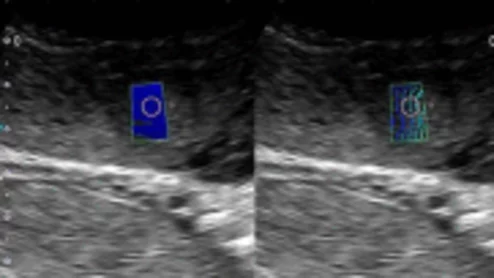

Ultrasound shear-wave elastography predict fetal growth abnormalities earlier than routine obstetric exams.

In recent years, shear-wave elastography has emerged as an imaging option that can provide greater detail into tissue health. Experts recently found that it is especially beneficial for fetal exams.